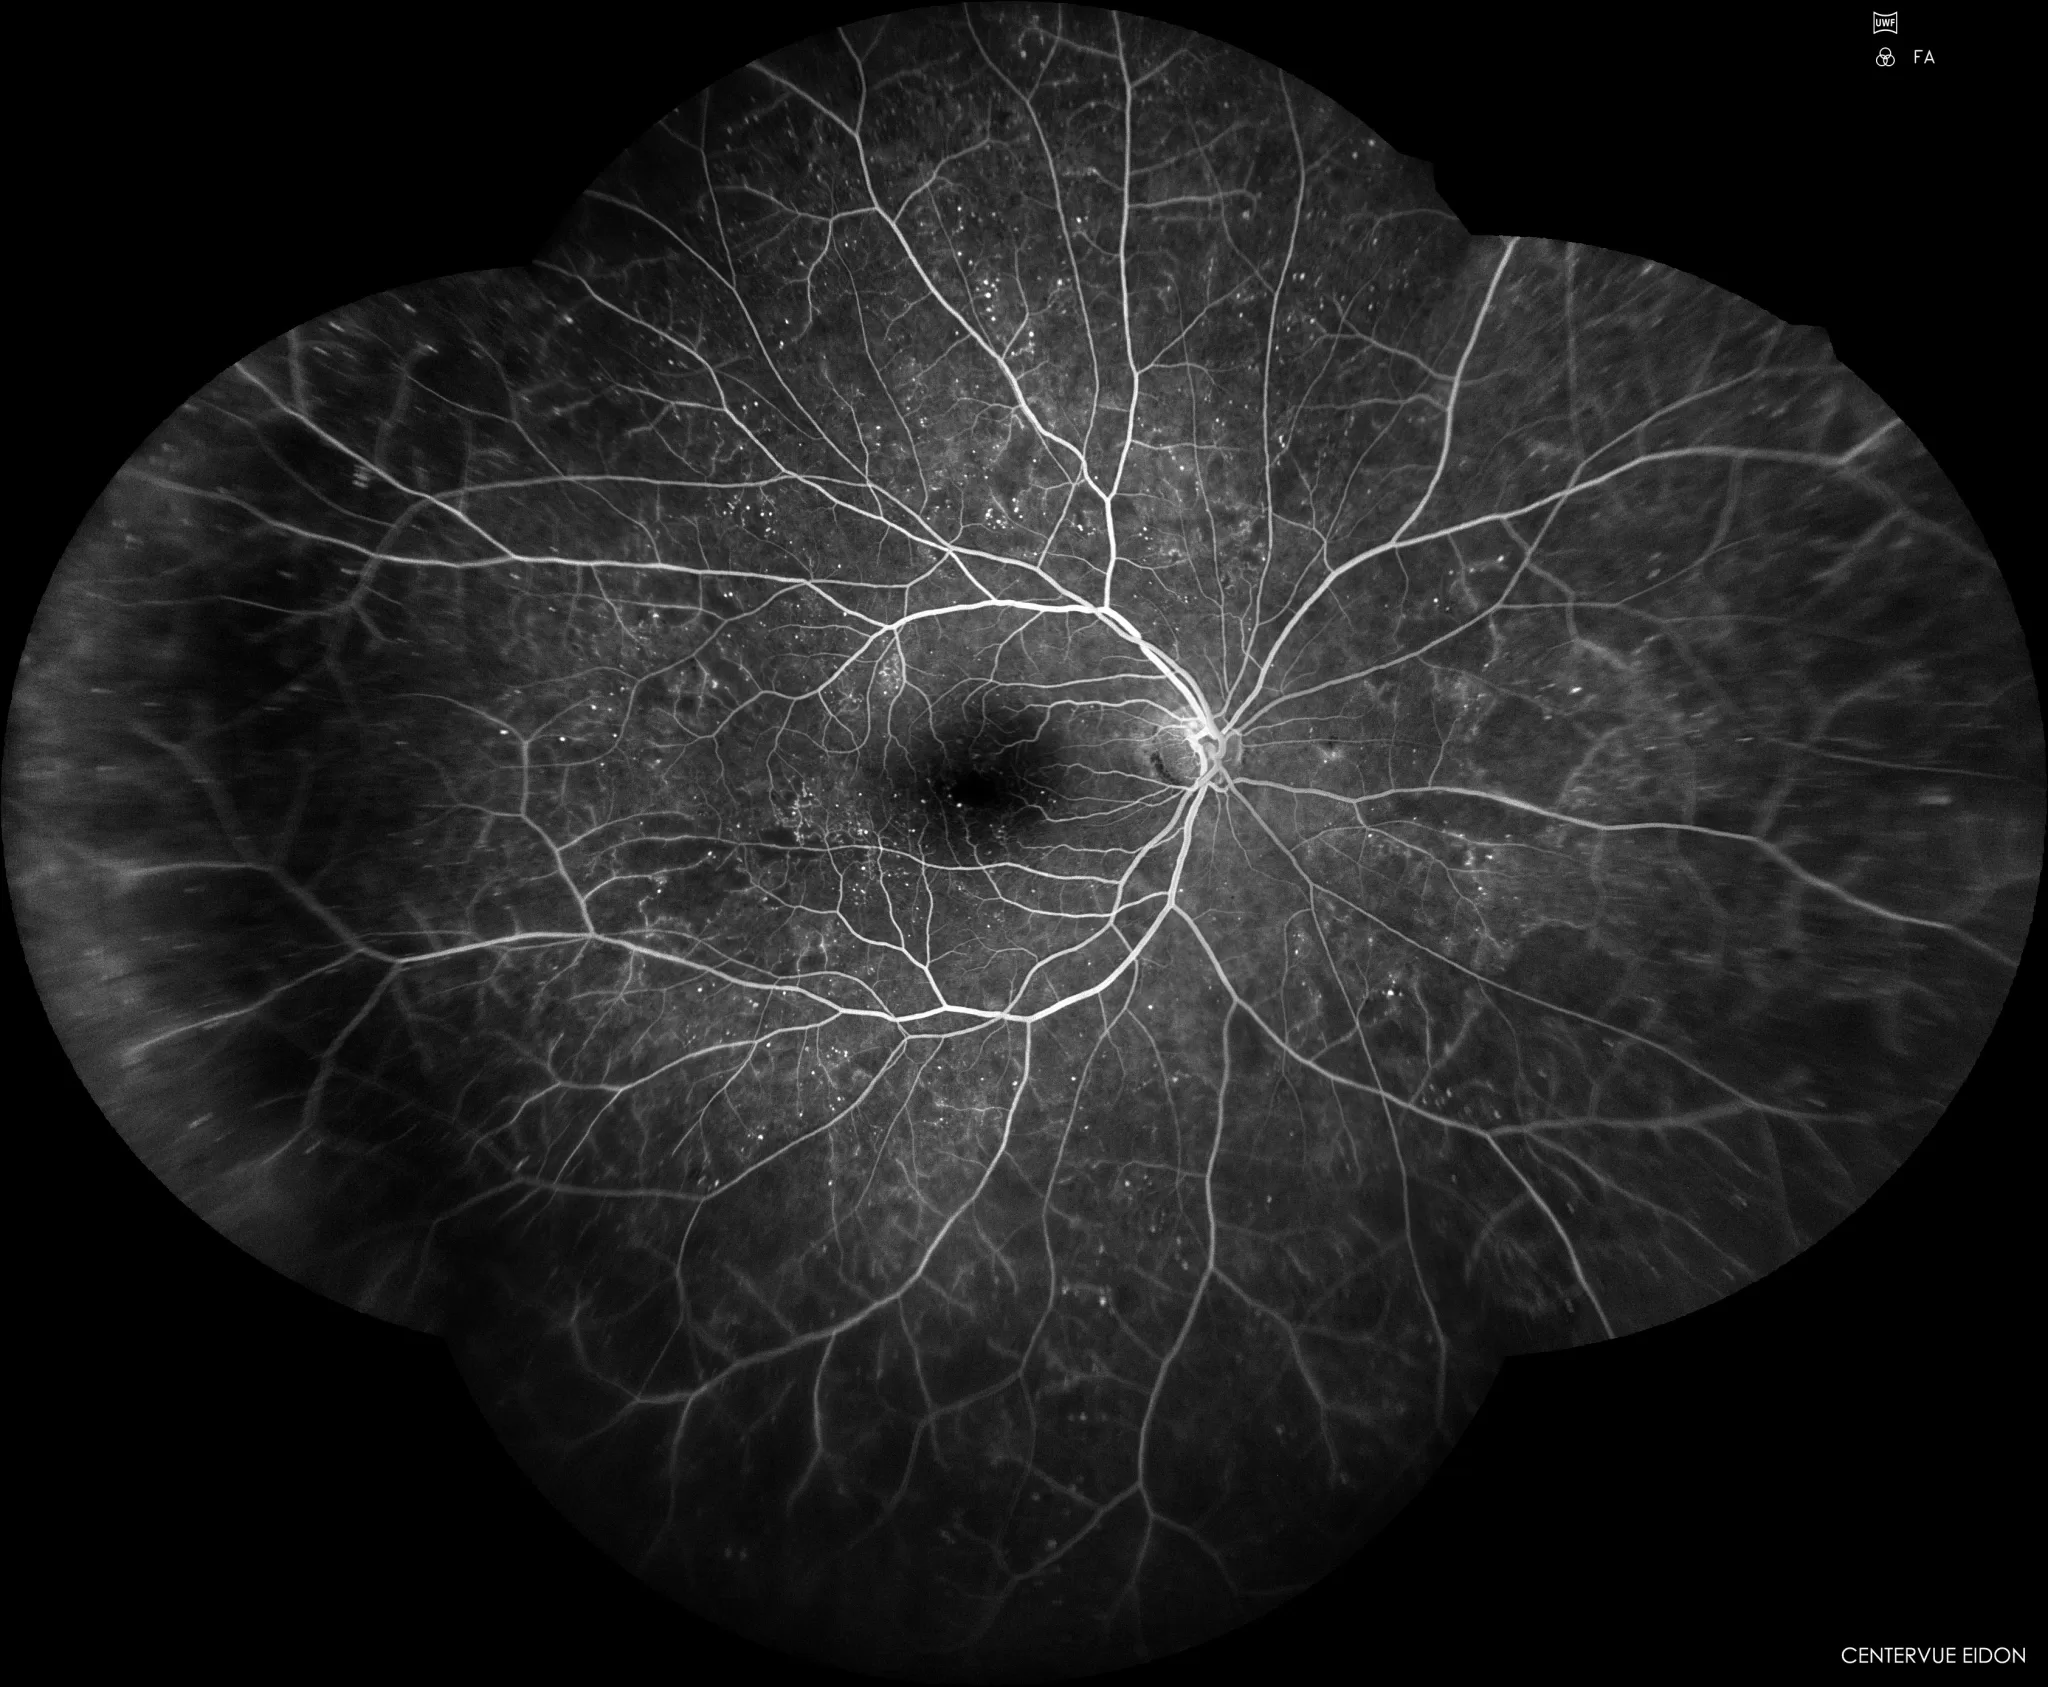

Cultura e Ciência

A cartografia e a retinografia — dois mapas, dois mundos, a mesma curiosidade.